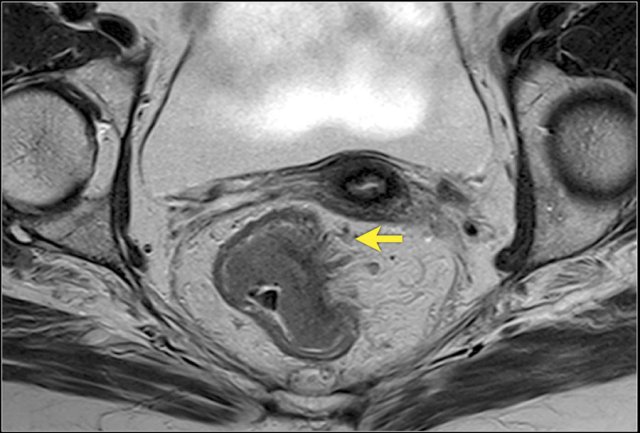

Assessment of MRF involvement after CRT

When a fat plane re-appears between the tumor bed and the MRF after CRT, the risk of persistent MRF

involvement is very small.

When

there is still diffuse infiltration of the MRF by intermediate tumor signal

after CRT, the risk for tumor invasion at histopathology is high (around

90%).

The

most difficult cases are those with diffuse fibrotic infiltration of the MRF.

In these cases, the risk for MRF positivity at histopathology

is around 50% [reference].

Images

Pre-CTR there is extensive invasion of the MRF from 4-8 o’clock (arrows). After CRT the tumor has undergone a fibrotic transformation and has retracted from the MRF. A fatplane has appeared with only some minor fibrotic stranding towards the MRF.

These are signs indicative of a tumor-free MRF at restaging (yMRF-)